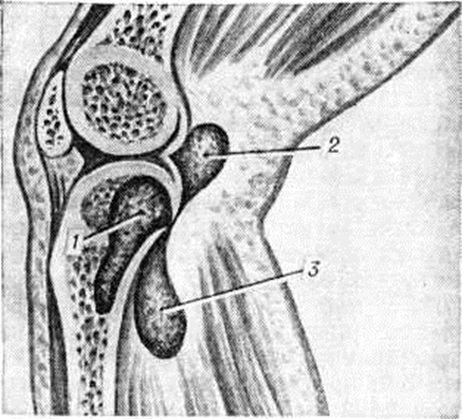

НатечникНатечник (синонимы: натечный абсцесс, холодный абсцесс, бугорчатый конгестивный абсцесс, туберкулёзный абсцесс) — скопление «холодного» (малоактивного) гноя, отграниченное соединительнотканной оболочкой, связанное со своим источником — туберкулёзным очагом в костях или суставах и имеющее склонность перемещаться по межмышечным и подапоневротическим пространствам. От Натечник следует отличать скопление «холодного» гноя вблизи очагов хронический остеомиелита, метатифозного спондилита, актиномикоза, сифилиса и другие Эти скопления — затеки (смотри полный свод знаний) образуются в результате прорыва гноя из первичного очага в окружающие мягкие ткани. В отличие от Натечник они не имеют склонности к миграции. Статистика. Натечник является характерной особенностью костно-суставного туберкулёза (смотри полный свод знаний Спондилит, Туберкулёз костей и суставов). Частота образования Натечник у больных костно-суставным туберкулёзом широко колеблется в зависимости от локализации процесса и состояния больных. По материалам П. Г. Корнева (1959), Натечник чаще всего наблюдается у больных туберкулёзом позвоночника (60%), туберкулёзным кокситом (38%), туберкулёзом локтевого сустава (25%), коленного сустава (20%) и плечевой кости (19%). Патогенез. В отличие от затёков Натечник образуется не в результате механического прорыва холодного гноя из очага в окружающие ткани. В 1837 —1839 годы Натечник И. Пирогов путём клинико-анатомических сопоставлений задолго до Ланнелонга (Одонтома М. Lannelongue, 1881) пришёл к выводу, что холодные нарывы являются следствием активного туберкулёзного процесса в мягких тканях, результатом распада в них «бугорчатого вещества». В последующем этот вывод нашёл подтверждение и развитие в трудах А. Натечник Чистовича (1936), П. Г. Корнева (1953), А. И. Струкова. По современным представлениям, Натечник представляет собой активную туберкулёзную гранулему, которая в случае недостаточности защитных механизмов организма разрастается, захватывая все новые ткани. Распространение (миграция) Натечник идёт по рыхлым соединительнотканным прослойкам, межмышечным и подапоневротическим пространствам, что обусловливает типичность локализации Натечник Натечник может возникнуть либо непосредственно близ поражённого отдела кости, либо вдали от него вследствие распространения туберкулёзного процесса по рыхлым соединительнотканным прослойкам. При поражении шейных и верхних грудных позвонков образуются подзатылочные (рисунок 1, 4) и заглоточные Натечник В грудном отделе позвоночника обычно не отмечается значительных продвижений Натечник Они остаются «сидячими» в виде «ласточкиных гнёзд» (термин предложен П. Г. Корневым в 1953 г.), а иногда выявляются паравертебрально в межлопаточной области (рисунок 1, 8). В поясничном отделе позвоночника Натечник иногда проникают кзади в поясничный треугольник (trigonum Petiti — рисунок 1, 5), в редких случаях — в толщу ягодичных мышц и даже в подколенную ямку (рисунок 1, в и 7). Наиболее часто, располагаясь внутри апоневротического влагалища большой поясничной мышцы, они выявляются в подвздошных областях и проникают через мышечную лакуну на бедро (рисунок 1, 7, 2, 3). Миграция Натечник наблюдается также и при туберкулёзном коксите вследствие наличия на бедре массивных мышечных групп. При поражении коленного сустава Натечник могут обнаруживаться на передней поверхности бедра под четырёхглавой мышцей, а при оститах проксимального конца большеберцовой кости спускаются вниз под икроножные мышцы и могут подниматься вверх: к суставу, инфицируя его извне (рисунок 2). Патологическая анатомия характерна для туберкулёзного процесса. При гисто л. исследовании находят специфические клеточные элементы по типу гранулемы с творожисто-некротическим распадом, гнойным расплавлением и образованием на её месте полости, окружённой оболочкой из туберкулёзных грануляций. Клиническая картина характеризуется общими и местными симптомами. Общая симптоматика обусловлена интоксикацией продуктами распада поражённых туберкулёзом тканей, особенно при больших скоплениях гноя, и проявляется снижением общего тонуса больного, ухудшением его состояния, потерей аппетита, падением веса, повышением температуры тела, иногда до 38,5°, нередко изменением английский показателей (анемия, ускоренная РОЭ, сдвиг лейкоцитарной формулы влево без заметного лейкоцитоза). |